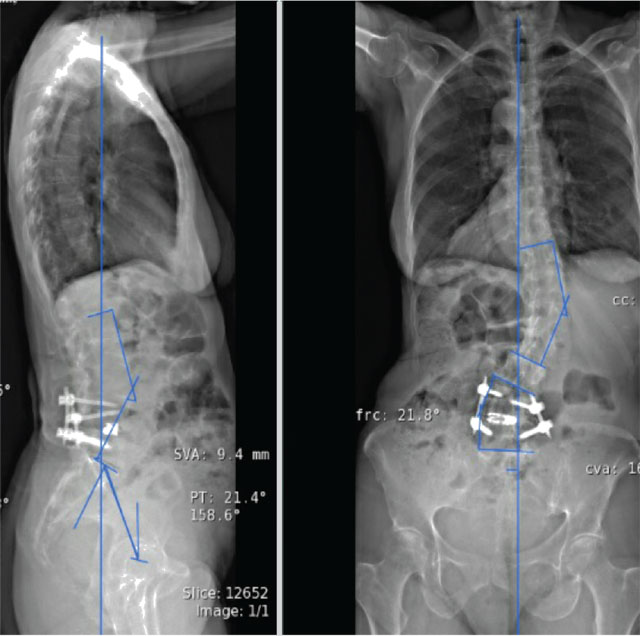

Pre- (A) and post- (B) operative radiographs demonstrating final reconstruction of adult degenerative spinal deformity.

Photo A:

Photo B: